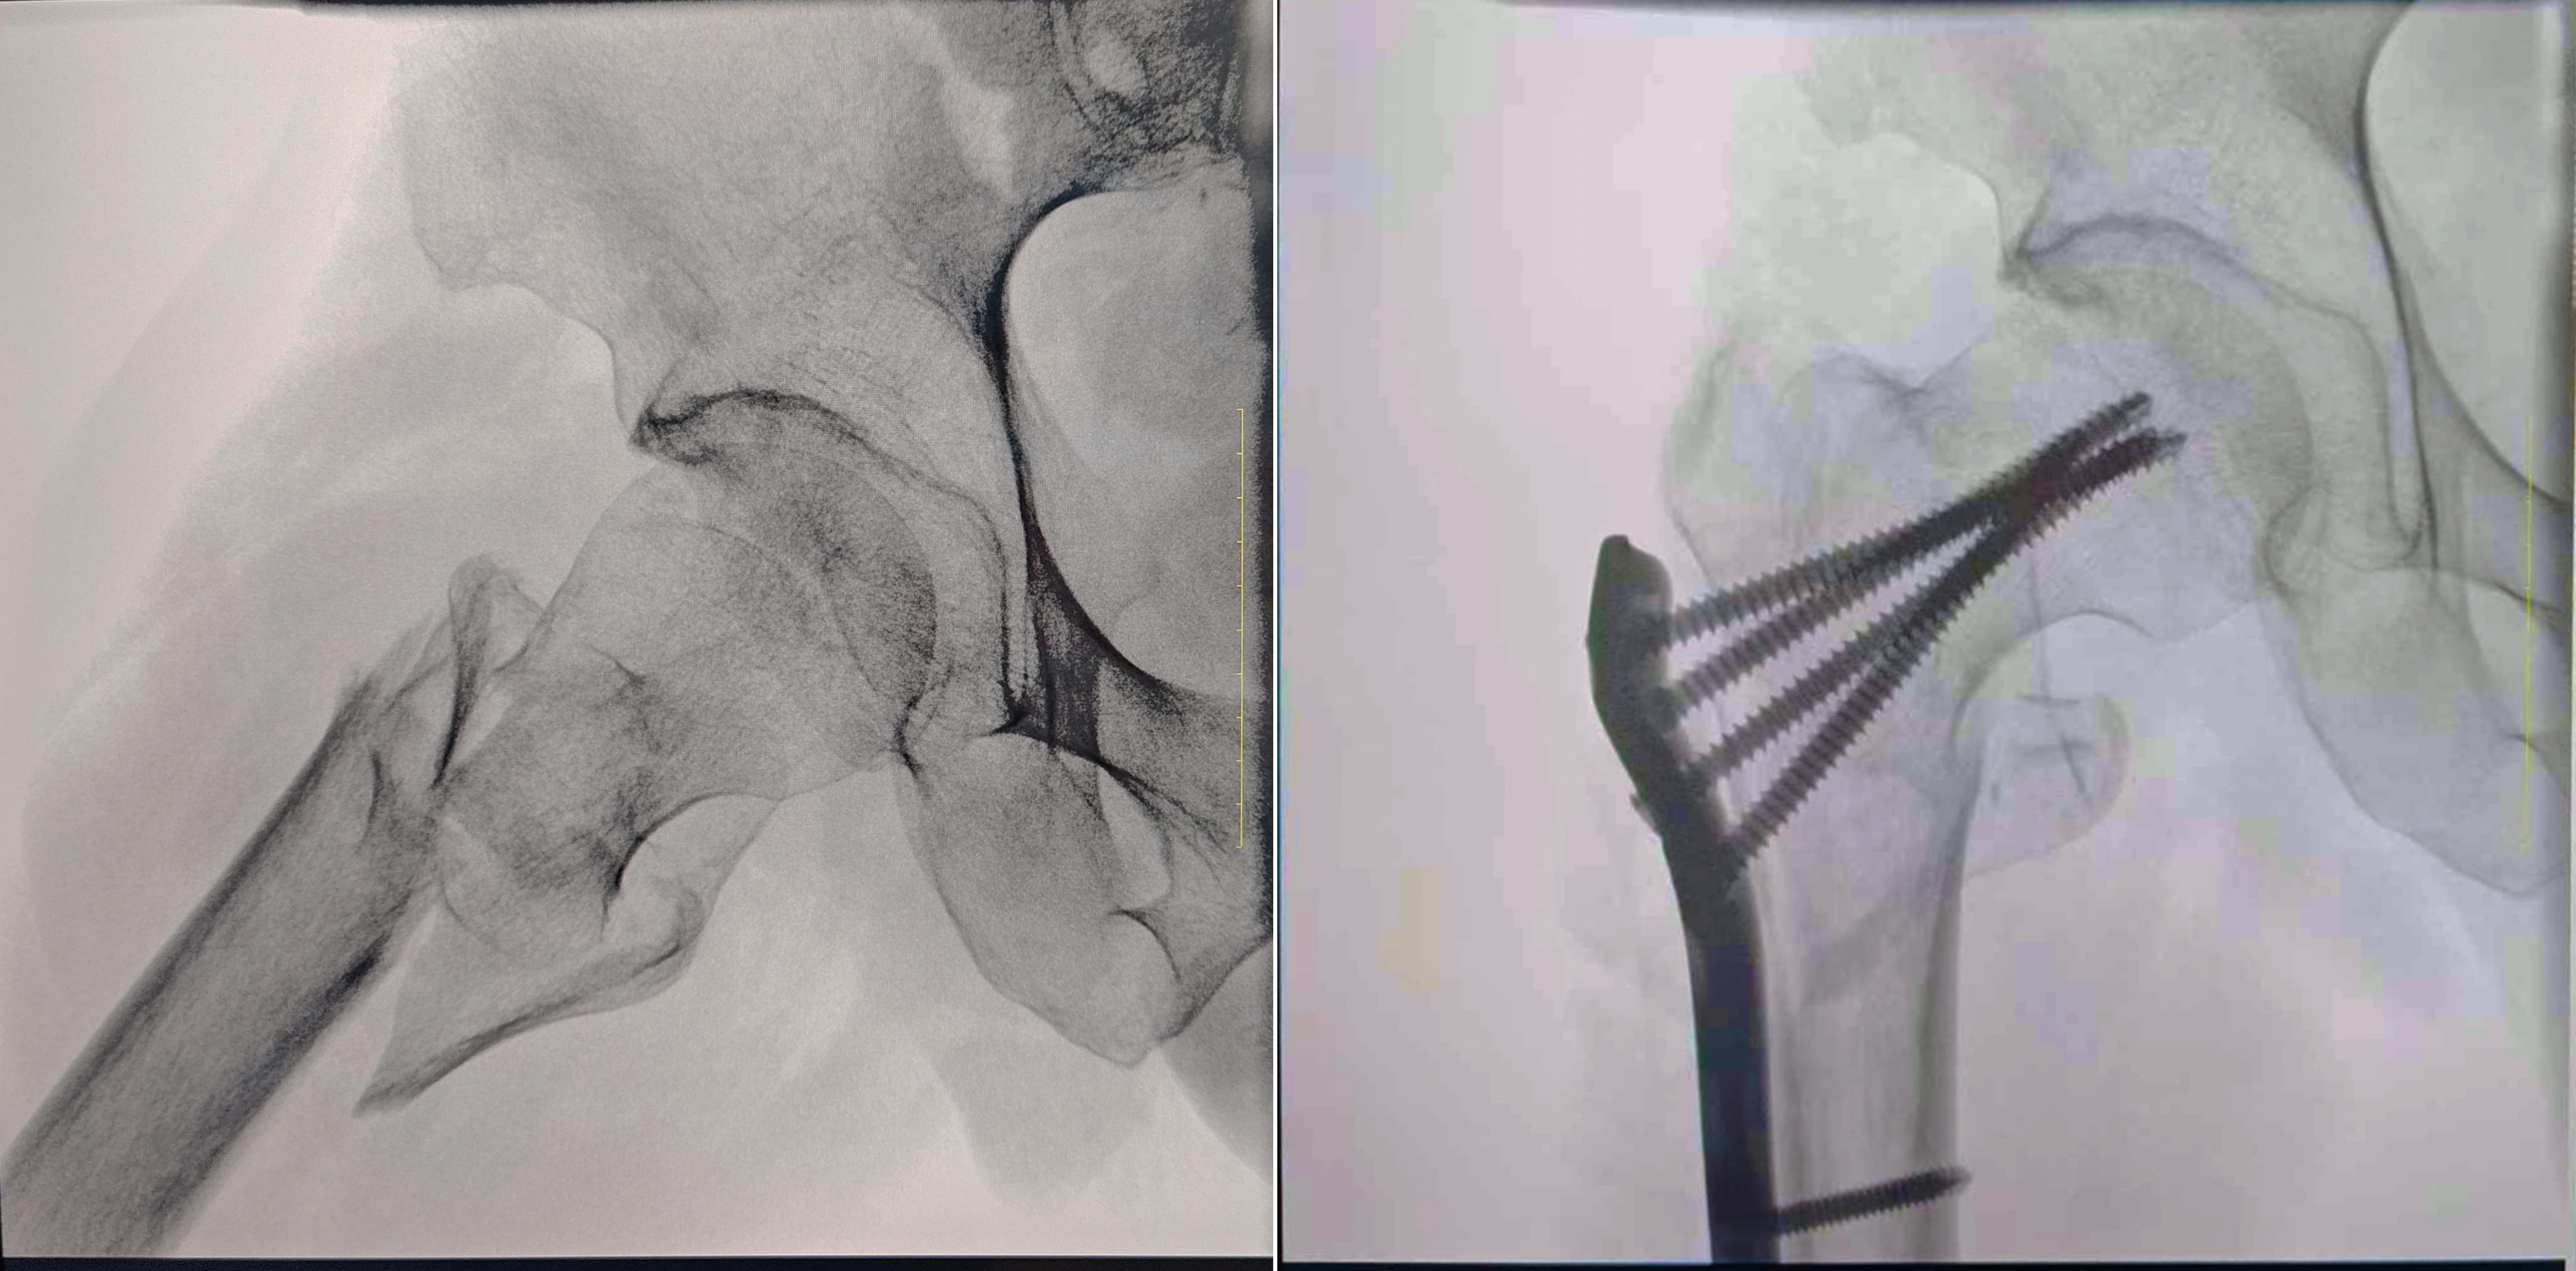

As the orthopedic surgeon's "other pair of eyes", the clarity and imaging range of the image have a significant impact on the surgeon's diagnosis and treatment decisions. The excellent hardware configuration and image processing performance of Perlove's large flat-panel integrated C-arm improves the clarity and details of intraoperative images, especially for pelvic acetabulum, long bone fractures and other surgeries that require large field of view imaging, the advantages of the equipment are particularly obvious. The following is an example of a fracture of the trochanter of the femur carried out by Pubei County Hospital of Traditional Chinese Medicine, which illustrates in detail how Perlove's large flat-panel all-in-one C-arm can help doctors realize more accurate diagnosis and treatment.

Clinical diagnosis: right femoral trochanteric fracture, accompanied by lower limb displacement and external rotation.

Surgery: internal fixation of right femur intertrochanteric fracture with incision and reduction

Large field of view, high-definition imaging, more comprehensive observation

Perlove's large flat-panel integrated C-arm adopts a 30CM×30CM flat-panel detector, which can help the surgeon comprehensively observe the patient's fracture separation and dislocation, and ensure the accurate formulation of surgical plans.![]()